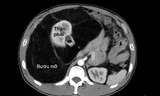

Ngày 15/5, thông tin từ Bệnh viện Đa khoa Xuyên Á cho biết, bệnh nhân H.T.L đã được chuyển đến cấp cứu tại đây. Sau khi thăm khám lâm sàng và thực hiện xét nghiệm, các bác sĩ đã chỉ định chụp MSCT 160 lát ổ bụng có cản quang. Kết quả cho thấy bệnh nhân bị tắc ruột non do viêm dính, tắc nghẽn cơ học bởi khối bã thức ăn lớn ứ đọng trong lòng ruột. Đây là tình trạng cần can thiệp khẩn cấp bởi nếu để kéo dài có thể gây hoại tử ruột, dẫn đến nhiễm trùng ổ bụng, sốc nhiễm trùng và nguy cơ tử vong cao.